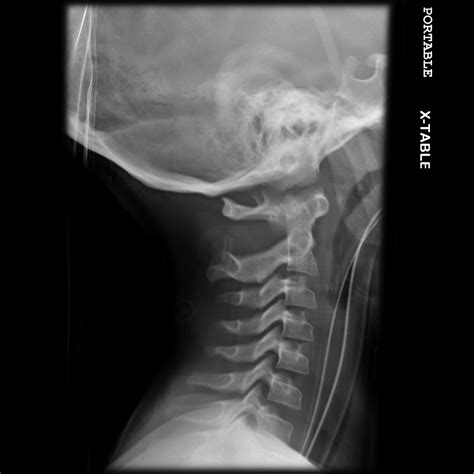

A cervical spine X-ray is a non-invasive diagnostic test that uses electromagnetic radiation to create images of the seven vertebrae located in the neck. These vertebrae, labeled C1 through C7, support the weight of the skull and facilitate head movement. When a radiologist or physician reviews these images, they are looking for specific markers of skeletal integrity.

• Proper Alignment: The vertebrae should form a smooth, gentle curve known as the lordotic curve. A "straightened" spine, often caused by muscle spasms, can indicate an underlying issue.

• Positioning: The technician will ask you to hold still in various positions—usually looking forward, sideways, and sometimes with the head tilted—to capture the spine from multiple angles.